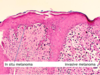

What is this?

Fibrocystic change: Bilateral, lumpy-bumpy, Blue domed cysts

What is this?

Fibrocystic change breast disease: Dilation of duct lobules, stromal fibrosis